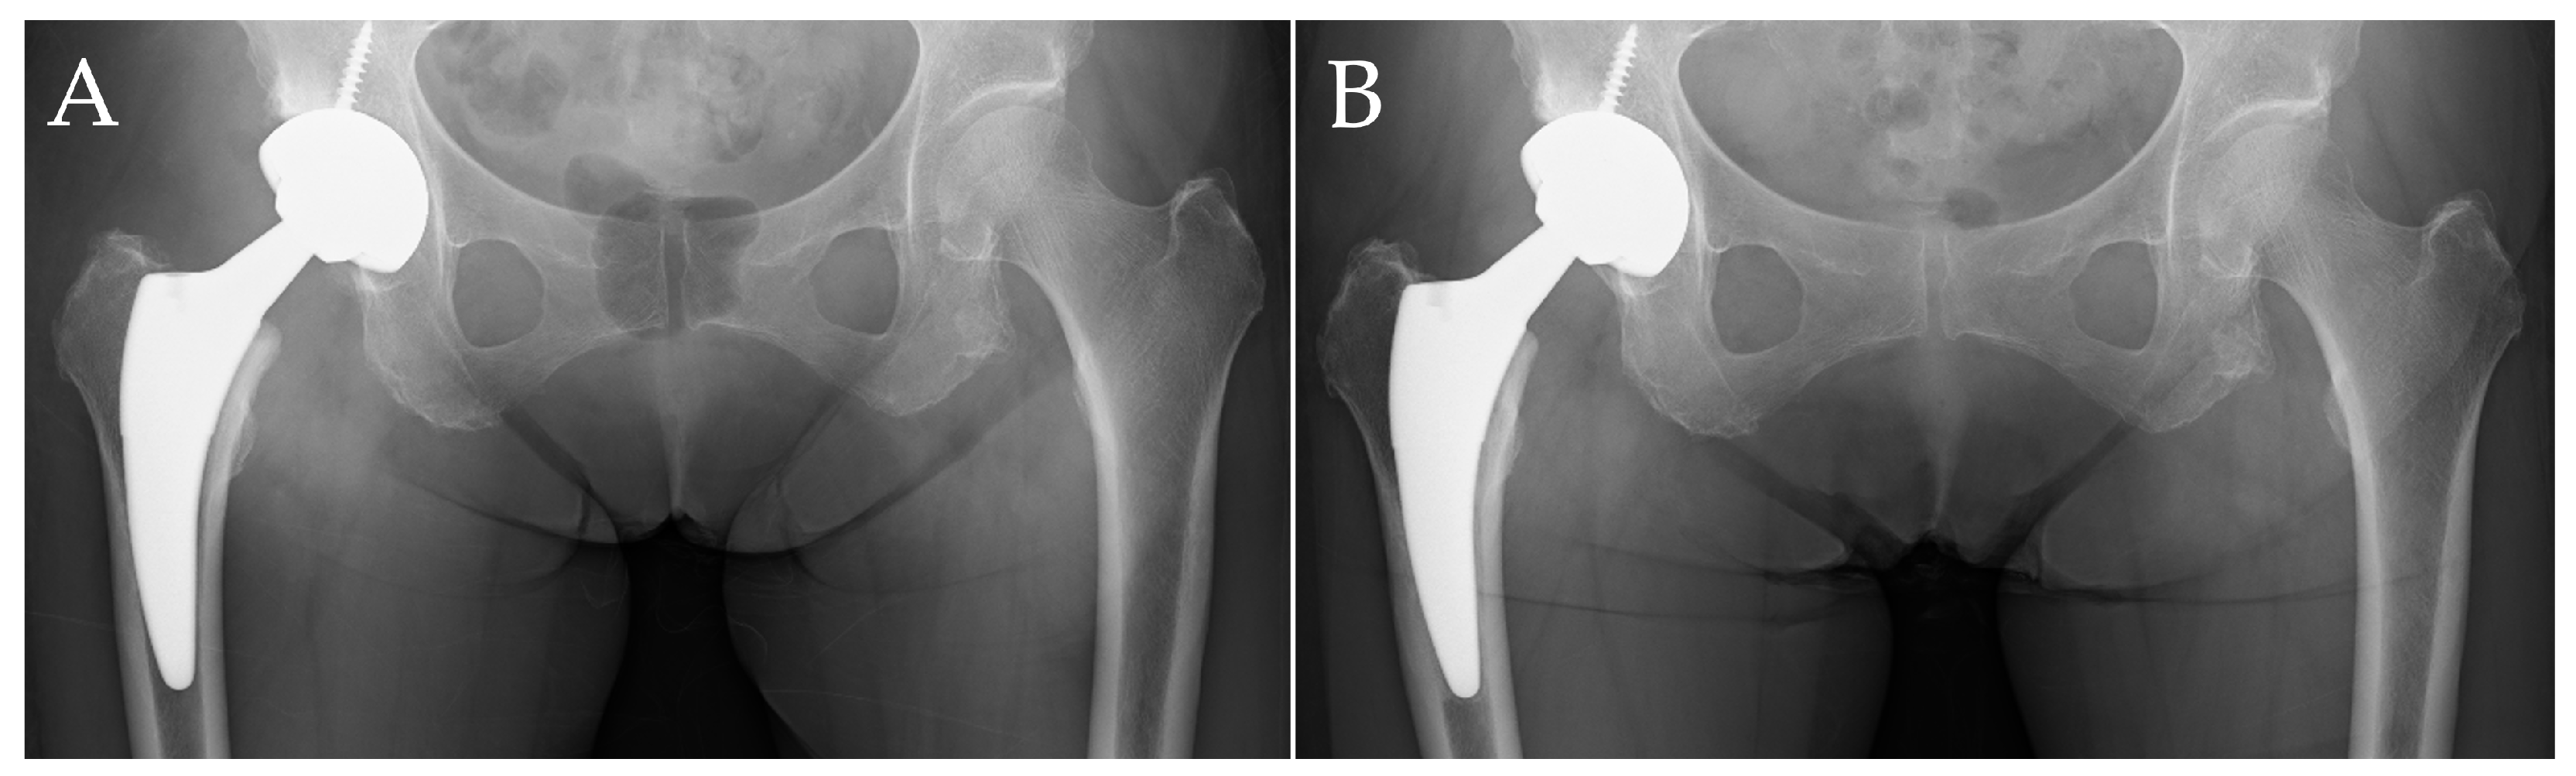

Figure 2 shows images of a case without evidence of stress shielding, taken immediately after surgery and at one year postoperatively. The patient was a 76-year-old woman with a comorbidity of systemic lupus erythematosus and osteoporosis induced due to glucocorticoid use. Osteoporosis treatment involved the use of denosumab. The THA was performed using a Fitmore stem and Continuum cup (Zimmer, Warsaw, IN, USA). Even in the images taken one year postoperatively, there were no findings of proximal femoral bone atrophy, and Engh’s classification was Grade 0 (Figure 2B).

Figure 2.

A representative case without evidence of stress shielding. Case of a 76-year-old female patient. (A) Anteroposterior radiograph of the hip immediately after surgery; (B) anteroposterior radiograph one year postoperatively. At one year postoperatively, no significant cortical bone thinning was observed, and there were no definitive indications of stress shielding.